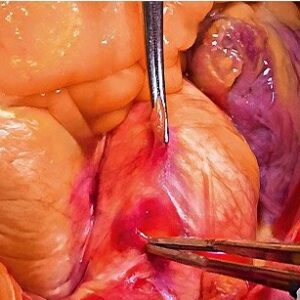

Cámara Quirúrgica – MCC-1000MD

Diseñada para ofrecer un gran nivel de detalle en aplicaciones de microcirugía, el cabezal de la cámara MCC-1000MD combina tres sensores CMOS Exmor™ R. Estos sensores, combinados con nuestra mejor tecnología de procesamiento de imágenes, permiten que la MCC-1000MD proporcione una sensibilidad de F20, una relación señalruido de 63 dB y una resolución horizontal de 1000 líneas de TV o más.